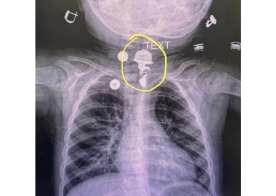

Həkimlər